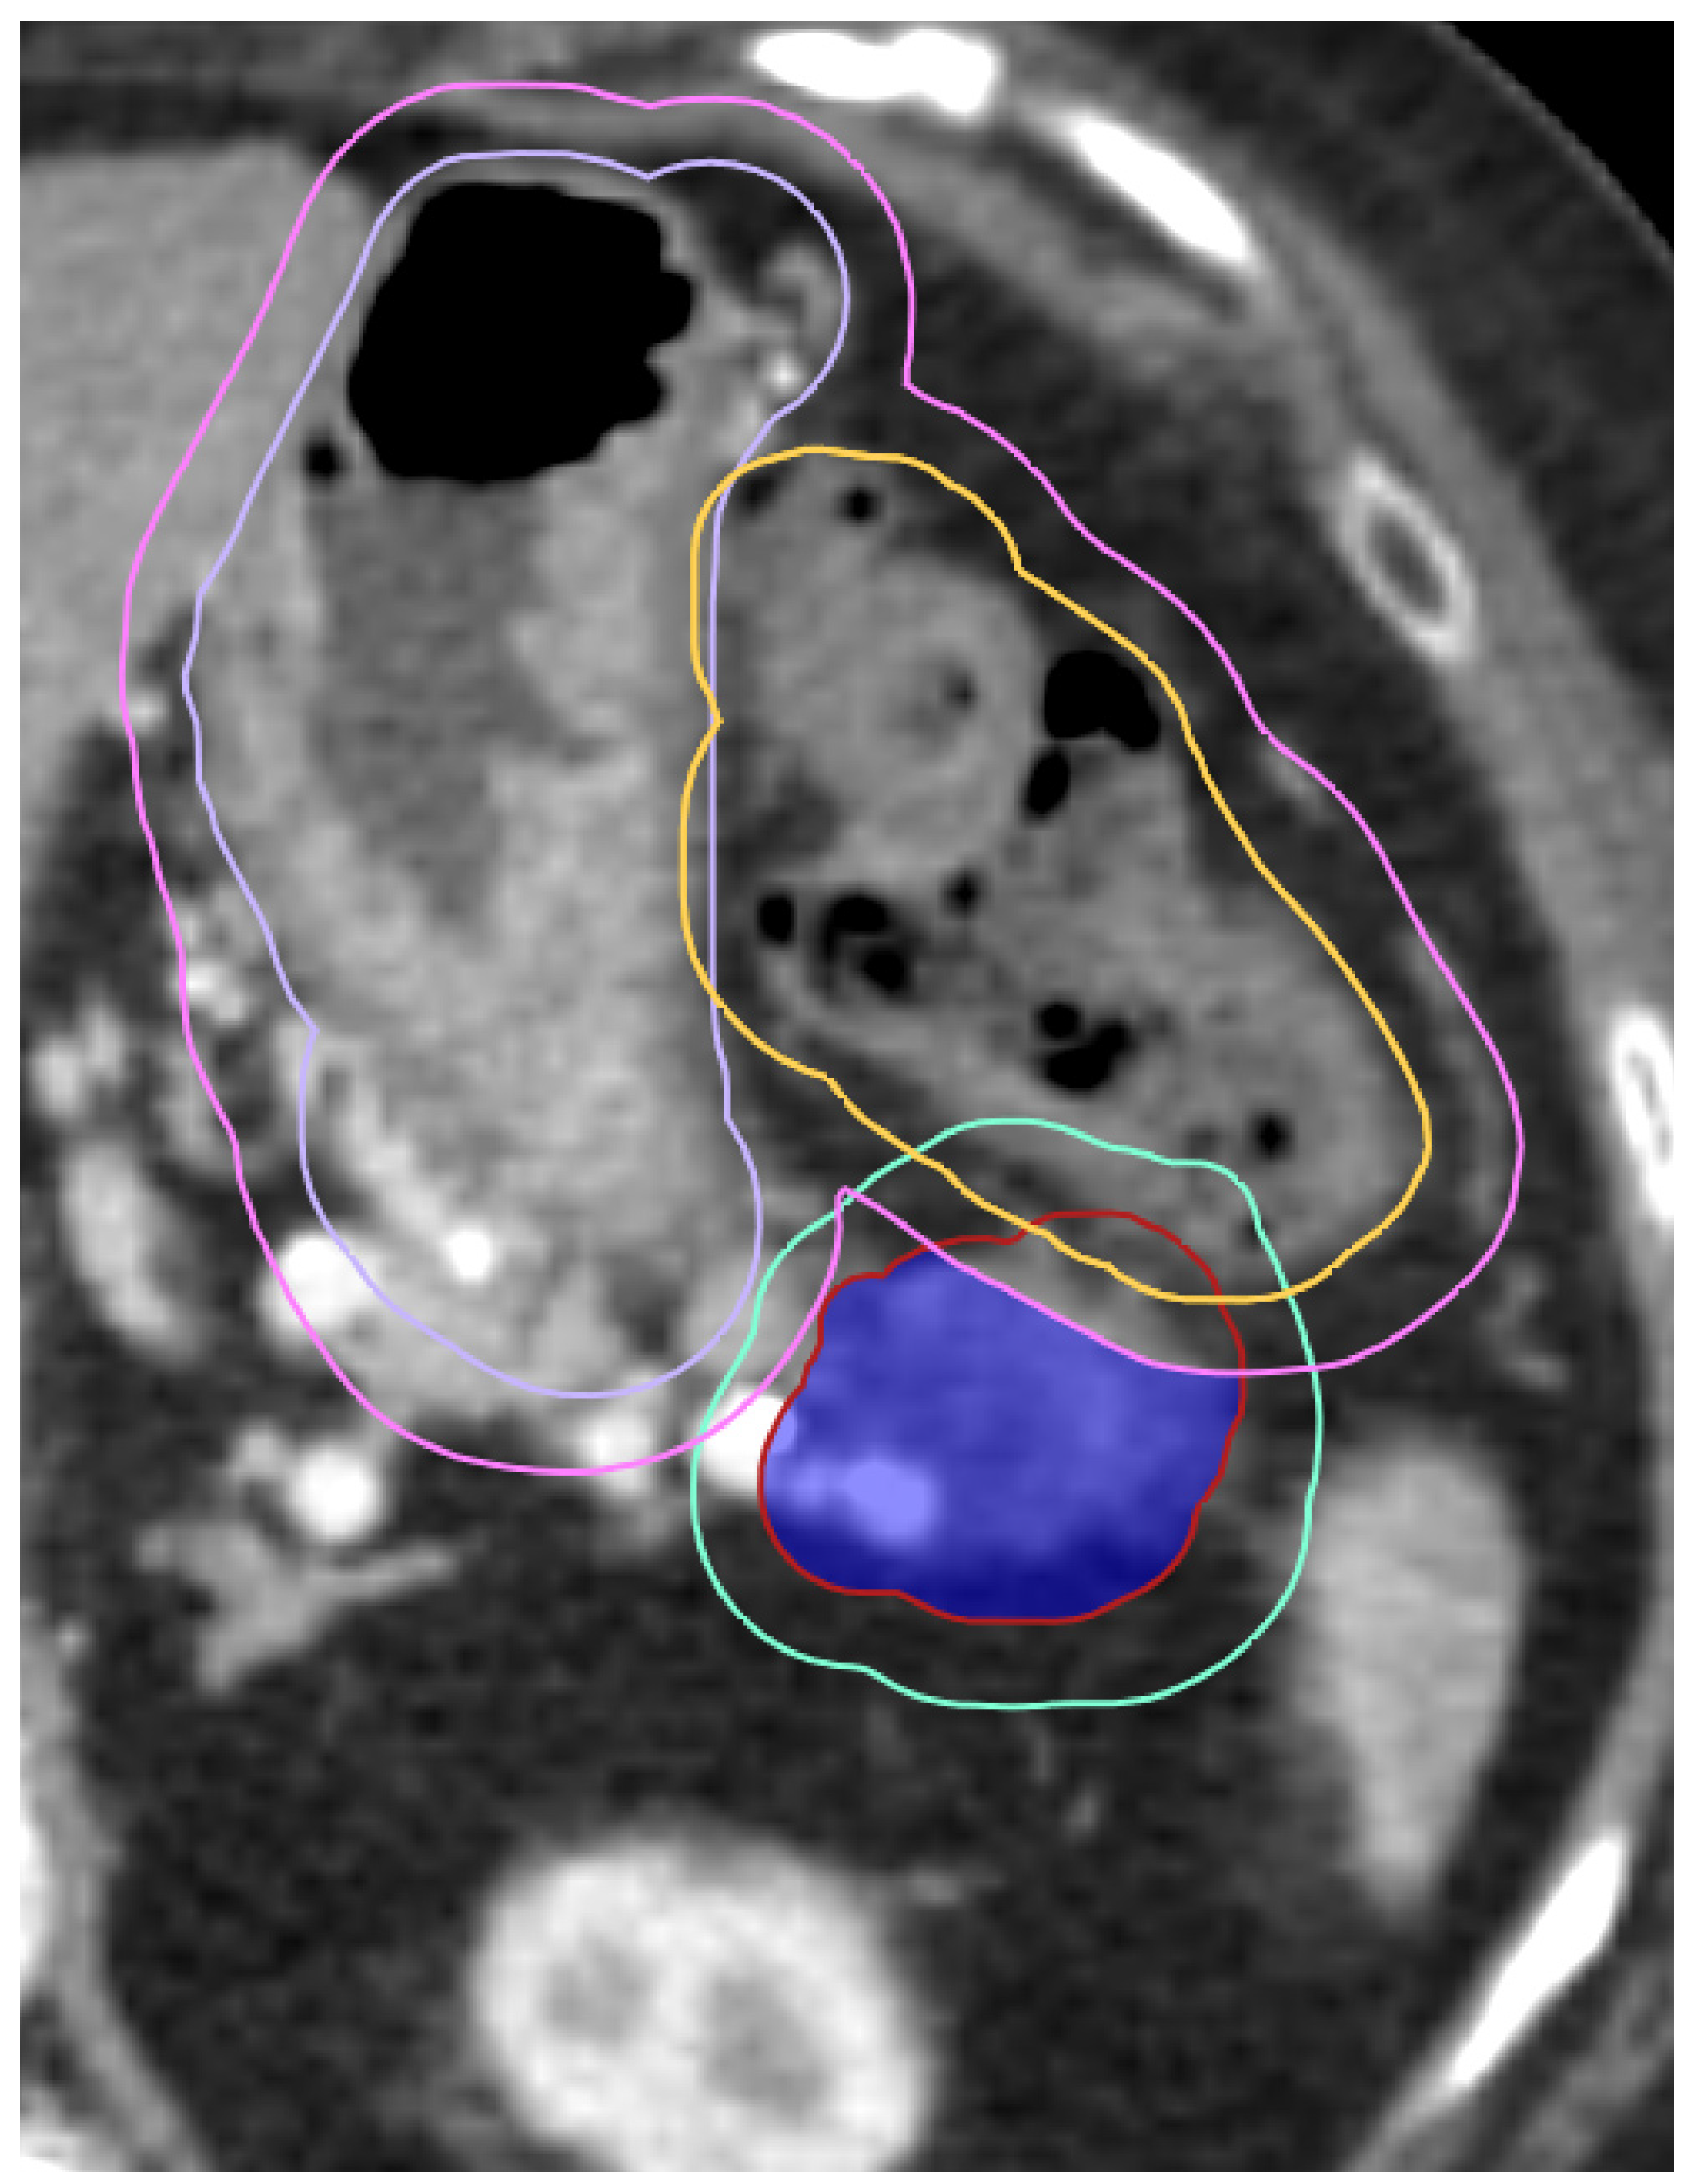

3.1. Case Study 1